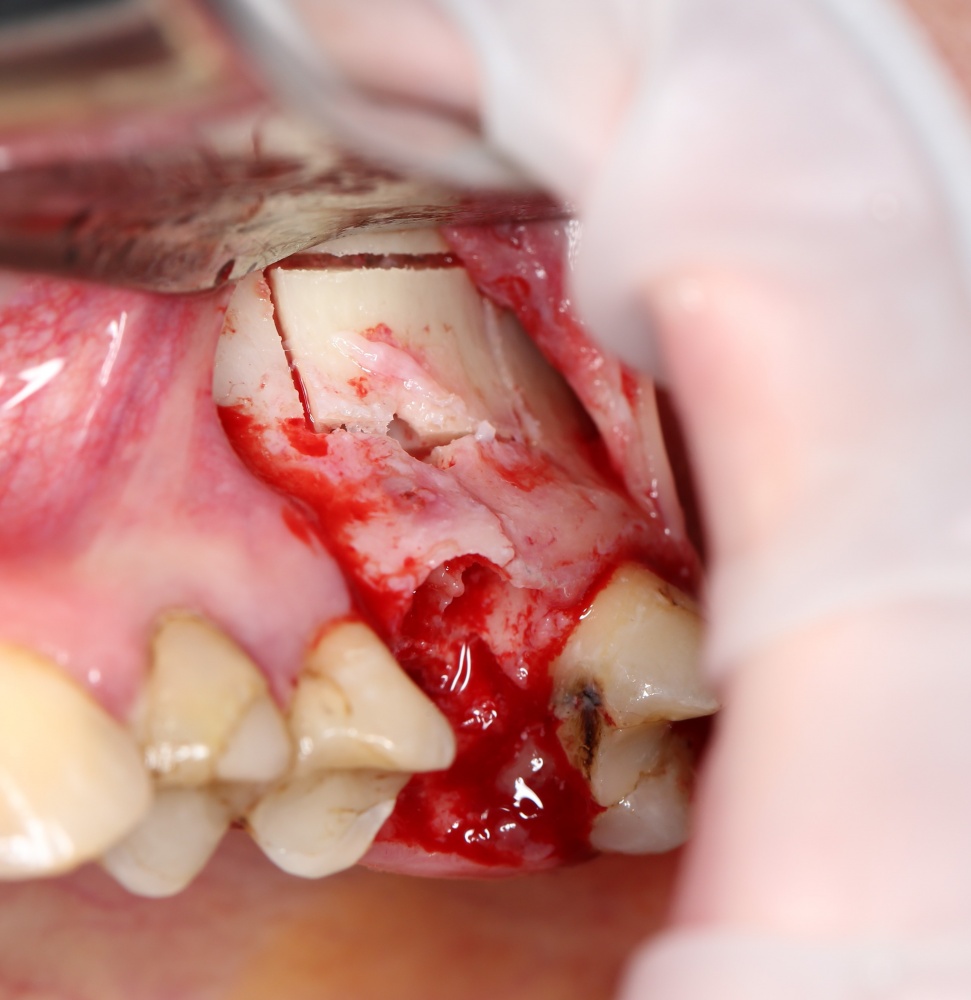

Как это делается, написано здесь>> и здесь>>, при этом существует ошибочное мнение, что большие апертуры доступа в верхнечелюстную полость тяжело заживают и оставляют дефекты кости. Покажу вам пример такого заживления.

Первая операция — мы не можем сразу поставить имплантат из-за почти полного отсутствия кости между полостью рта и дном верхнечелюстной пазухи:

Как видите. восстанавливается всё очень легко, никаких дефектов не остаётся, но при этом мы получаем важное преимущество: достаточную свободу движений при формировании субантральной полости и хороший визуальный контроль за состоянием слизистой оболочки. Никакая нажопная оптика или суперпупермикроскоп, к сожалению, не обеспечат подобный контроль при закрытом синуслифтинге. Да, операция получается травматичнее и масштабнее, чем «закрытый» синуслифтинг, но несёт в себе гораздо меньше рисков.